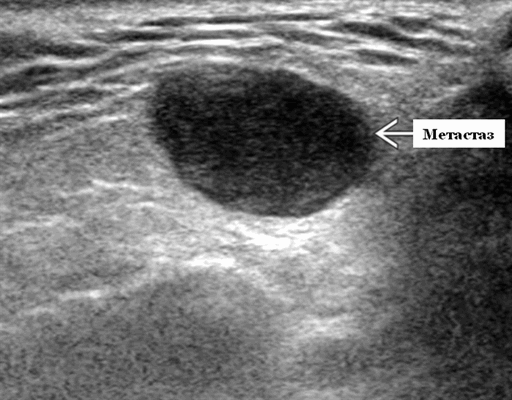

- Одиночные или множественные гипоэхогенные образования при известном распределении внутрипаротидных лимфоузлов.

- На ультразвуковом сканировании образование четко или плохо определено (экстранодальное распространение)

- На УЗИ определяется аномальная внутренняя архитектура ± эхогенные ворота, эхогенность однородная или неоднородная с внутренними кистозными участками в некротических узлах

- ± Метастатические шейные лимфатические узлы

Результаты ультразвукового исследования слюнной железы

Серошкальное УЗИ. Одиночные или множественные гипоэхогенные образования в известном распределении внутрипаротидных лимфоузлов. Хорошо выраженный или слабо окаймленный (экстранодальное распространение). Экстранодальное распространение. Обратите внимание на местную инвазию интрапаротидной наружной сонной артерии (ВСА), ретромандибулярной вены или экстрапаротидных мягких тканей. Аномальная внутренняя архитектура ± эхогенные ворота. Однородный или неоднородный вид с внутренними кистозными участками в некротических узлах ± метастазы в шейные лимфатические узлы